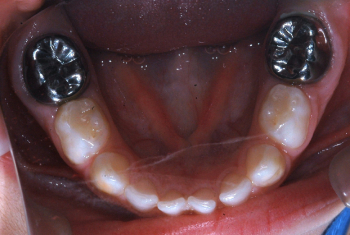

Antes: